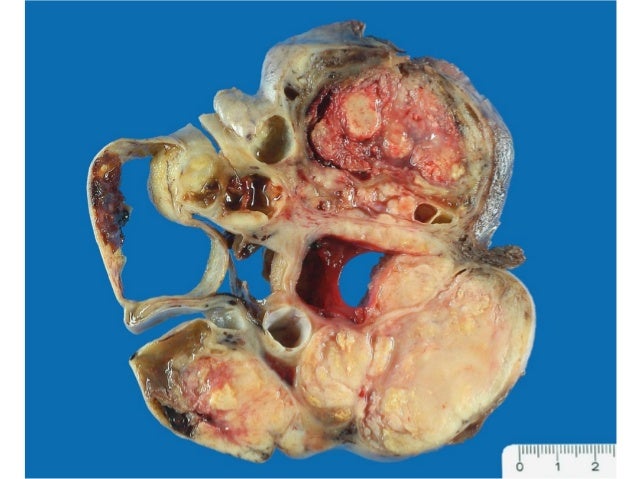

Macroscopicamente un ovario poliquistico observándose cada quiste en su interior A nivel del microscopio veremos los quistes foliculares y el engrosamiento de lo que es la túnica albugínea.

CISTOADENOCARCINOMA SEROSO. Neoplasia invasiva varía desde bien diferenciados a mal diferenciados. 60% de las neoplasias ováricas. Tamaño variable, 2/3 son bilaterales, sólido o quísticos. Arquitectura papilar, glandular o sólida, glándulas irregulares, las papilas muy ramificadas e hipercelulares, cuerpos de psammoma (característicos de los CA papilares). Graduación basada en la arquitectura.